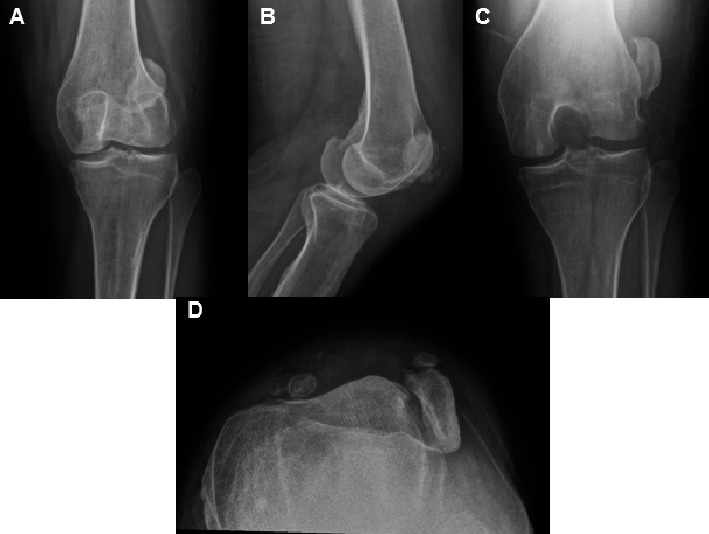

The following case report demonstrates a case of a chronic irreducible patellar dislocation, age-indeterminate associated with a large medial patellar avulsion fracture that was treated with a vastus medialis obliquus advancement following an extensive lateral release. This case is the only known report of this kind in the literature. The patient is a 41-year-old Caucasian female who presented to the clinic with an age-indeterminate, chronically dislocated patella. She has a past medical history of hypertension and ischemic stroke 1 year prior to presentation, leading to expressive aphasia and lower extremity weakness in addition to patellar instability dating back to age 13. An unsuccessful patellofemoral reduction was performed at an outside clinic, and she was placed in a knee immobilizer and referred to our office. Clinically, the patient had limited knee range of motion with a fixed lateral patellar dislocation that was confirmed on imaging. This case report demonstrates a surgical reduction technique that can be utilized by orthopedic surgeons for chronic patellar dislocations that are not amenable to routine patellar instability surgeries due to the contraction of surrounding soft tissue, chronic bone abnormalities, and position of the chronic dislocation. An extensive lateral release followed by vastus medialis obliquus advancement was performed to center the patella within the trochlear groove and to allow for stable articulation throughout range of motion. The patient was able to regain painless, full range of motion of her knee postoperatively with patellar stability noted on both physical exam and radiographic imaging.

Abstract Image